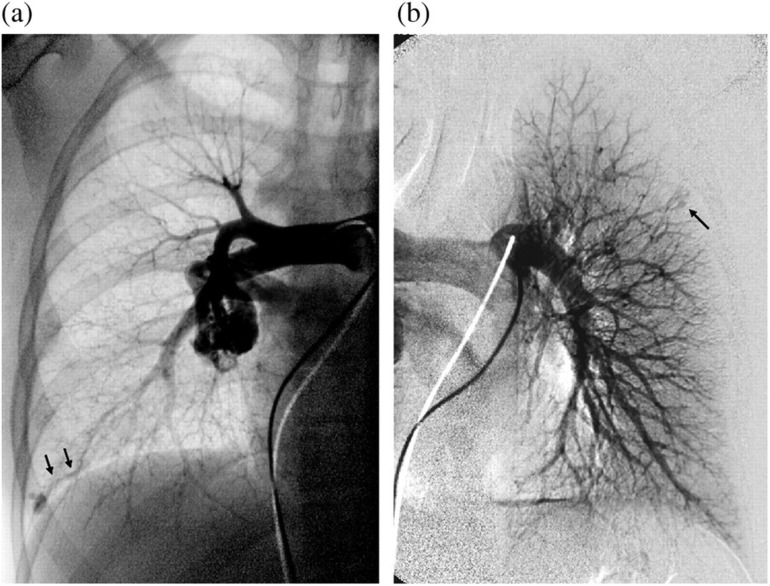

肺动脉动静脉畸形(pavm)的供血动脉长度为3mm或以上,已被证明与矛盾栓塞和严重的神经系统并发症有关。因此,通常建议闭塞这种大小的供血动脉,而较小的供血动脉通常不予治疗。然而,神经系统并发症也被描述在小的pavm患者中,并且不可能根据供血动脉的大小对风险进行分层,因此没有证据表明3mm是可能引起并发症的供血动脉的临界大小。此外,众所周知,随着时间的推移,pavm及其供血动脉可能会扩大。此外,栓塞小供血动脉将最大限度地减少矛盾栓塞的风险,并减少对这些患者进行CT随访控制的需要。两个病例证明了栓塞小供血动脉的可能性。

Pulmonary arteriovenous malformations (PAVMs) with feeding arteries of 3 mm or more have been shown to be associated with paradoxical embolization and serious neurologic complications. Therefore it is generally recommended to occlude feeding arteries of this size, while smaller feeding arteries often are left untreated. However, neurologic complications have also been described in patients with small PAVMs, and it has not been possible to stratify risk by size of feeding artery and thus there is no evidence that 3 mm is the critical size of the feeding artery potentially giving complications. Further, it is well-known that with time PAVMs and their feeding arteries may enlarge. Also, embolization of small feeding arteries will minimize the risk of paradoxical emboli and reduce the need for CT follow-up controls in these patients. Two cases demonstrate the possibility to embolize small feeding arteries.